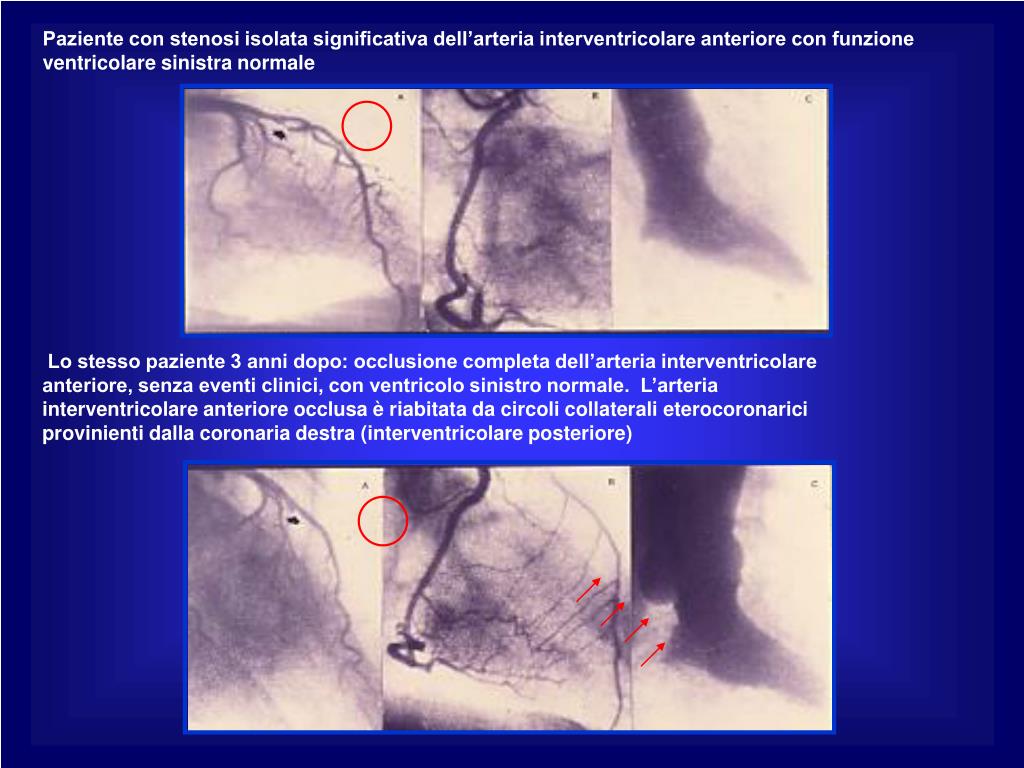

38. Paziente con stenosi isolata significativa dell’arteria interventricolare anteriore con funzione ventricolare sinistra normale Lo stesso paziente 3 anni dopo: occlusione completa dell’arteria interventricolare anteriore, senza eventi clinici, con ventricolo sinistro normale. L’arteria interventricolare anteriore occlusa è riabitata da circoli collaterali eterocoronariciprovinienti dalla coronaria destra (interventricolare posteriore)